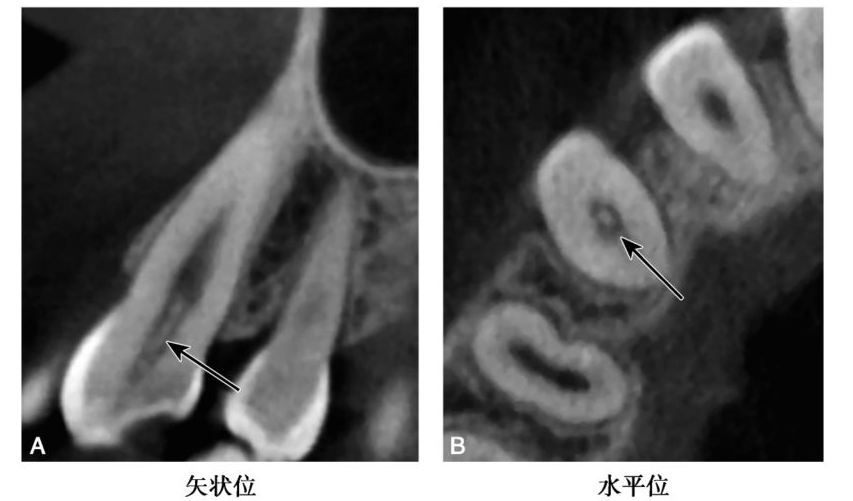

(3)弥散性钙化表现为正常的髓室及根管轮廓的消失(图5)。

图2-2-5 A1弥散性钙化

CBCT示A1髓室、根管正常影像消失,呈均匀近牙本质密度影(白色箭头)

(4)有些较大的髓石可能影响根管口的探查,如术前不熟悉根管系统的解剖特点,可能造成医源性意外(图6)。

图2-2-6 B1弥漫性钙化伴侧穿

CBCT矢状位示B1弥散性钙化,自舌侧窝至唇侧牙颈部见侧穿(白色箭头)